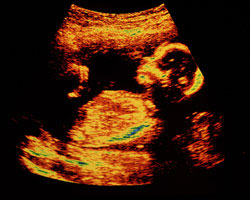

Gostavas de ver uma aproximação de como é o teu bebé esta semana? Aqui tens a imagem de uma ecografia de 16 semanas, além de um magnífico vídeo como feto em movimento. Não percas!

Ecografia 16 semanas